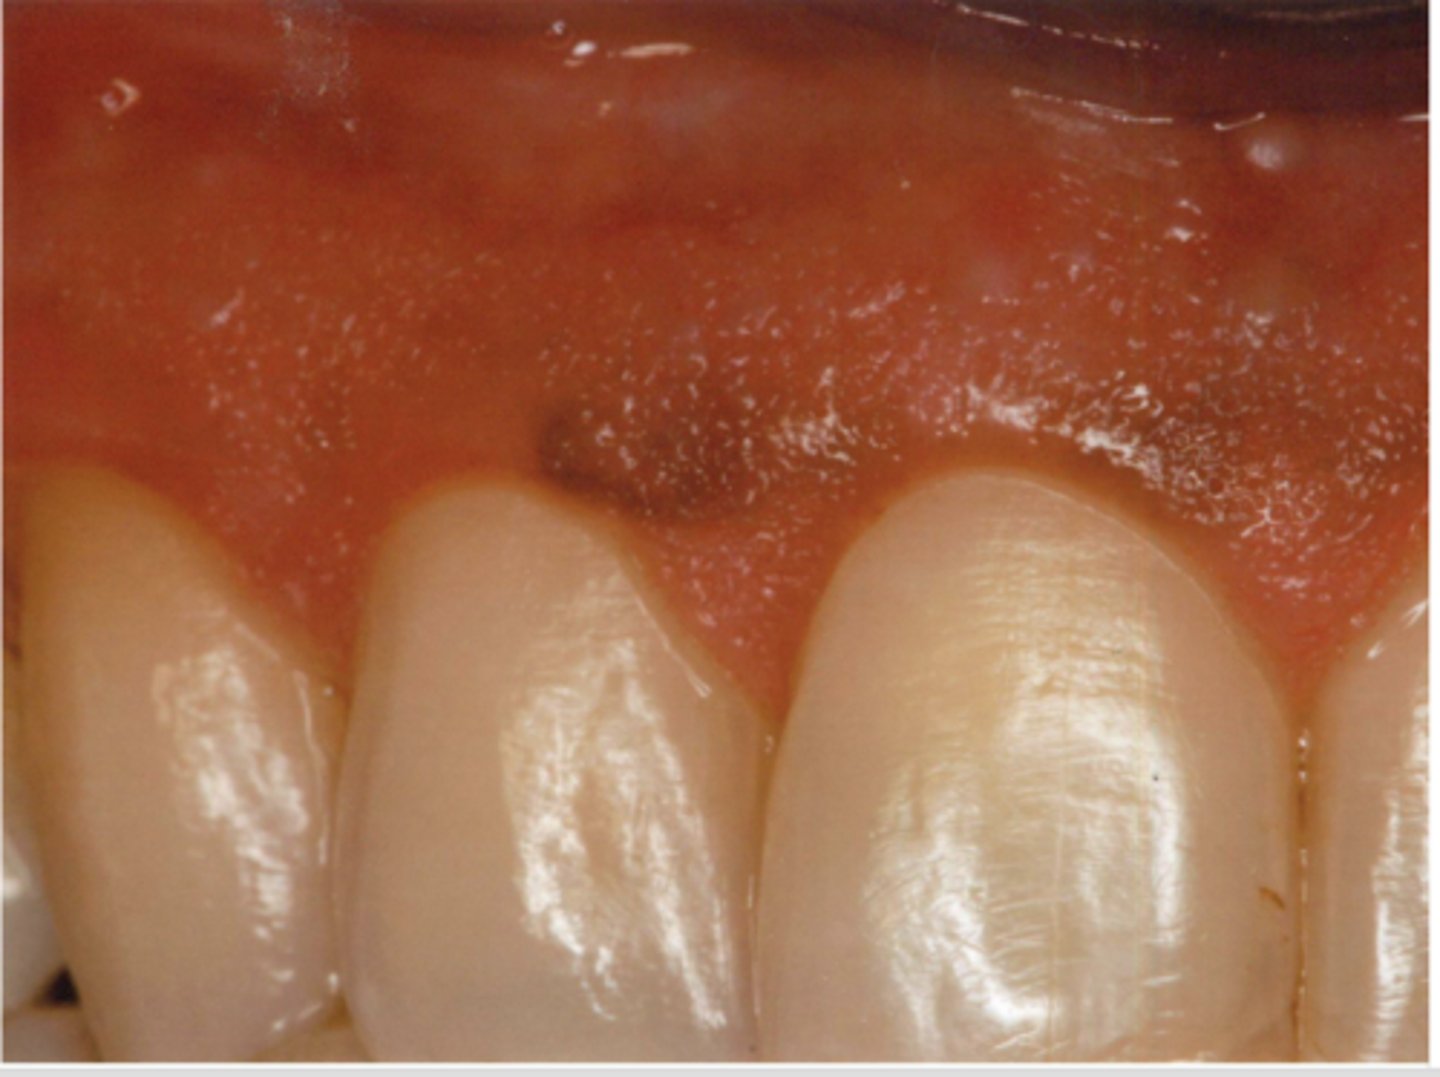

What type of pigmented lesion?

melanotic macule

These are characteristics of what pigmented lesion?

- Discrete, solitary (usually), tan to brown painless macule

- Most commonly found on lip mucosa then gingival/palatal mucosa, then buccal mucosa

- If multiple, explore...

oral melanotic macule

Which type of pigmented lesion has these histopathologic features?

- Increased level of melanin in basal and para-basal layers of epithelium and connective tissue